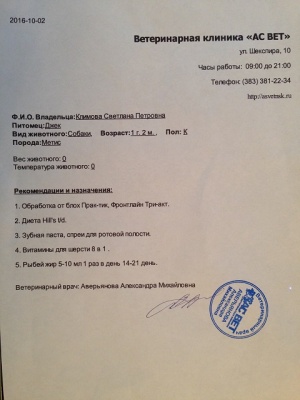

– прием дерматолога, врач Аверьянова Александра Михайловна, клиника АС Вет (400 руб.), вет диета Hills t/d для снятия налета с зубов (1979 руб.), Милпразон (антигельминтный препарат) 400 руб. (скидка на сумму чека 15%) (чек 3, копия чека 3, лист назначений – документ 3) – 2362 руб.

– прием дерматолога, врач Аверьянова Александра Михайловна, клиника АС Вет (400 руб.), вет диета Hills t/d для снятия налета с зубов (1979 руб.), Милпразон (антигельминтный препарат) 400 руб. (скидка на сумму чека 15%) (чек 3, копия чека 3, лист назначений – документ 3) – 2362 руб.

По результатам осмотра 02.10.2016 (врач Аверьянова А.М., клиника АС Вет) пока рекомендована очередная обработка от блох, витамины, гигиена полости рта, диета Hills t/d для снятия налета с зубов. Если не будет видимого блестящего результата в течение месяца, придется проходить более глубокое обследование.

По результатам осмотра 02.10.2016 (врач Аверьянова А.М., клиника АС Вет) пока рекомендована очередная обработка от блох, витамины, гигиена полости рта, диета Hills t/d для снятия налета с зубов. Если не будет видимого блестящего результата в течение месяца, придется проходить более глубокое обследование.